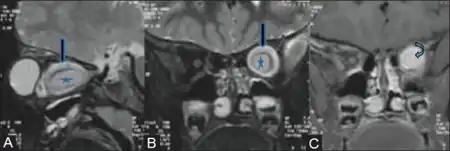

| Magnetic resonance image of a large retrobulbar optic nerve tumor causing massive proptosis | |

Optic nerve gliomas are diagnosed using magnetic resonance imaging (MRI) and CT scans.[6] The tumor adopts a fusiform appearance, appearing wider in the middle and tapered at the ends.[6] Enlargement of the optic nerve along with a downward kink in the mid-orbit is usually observed.[6] While CT scans allow for optic nerve evaluation, MRI allows for intracranial evaluation to observe if the tumor has extended to other regions such as the optic chiasm & hypothalamus.[7]